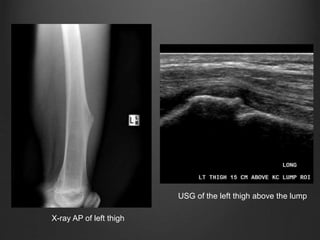

ULTRASONOGRAPHY

• Ultrasonography can be applied to analyze

the cartilaginous cap of an osteochondroma.

• The cap appears as a hypoechoic layer

covering a hyperechoic underlying bone.

• Ultrasonography is also valuable in the

diagnosis of bursitis and other complications

associated with osteochondromas, such as

arterial or venous thrombosis, as well as

aneurysm and pseudoaneurysm formation.

X-ray AP of left thigh

USG of the left thigh above the lump